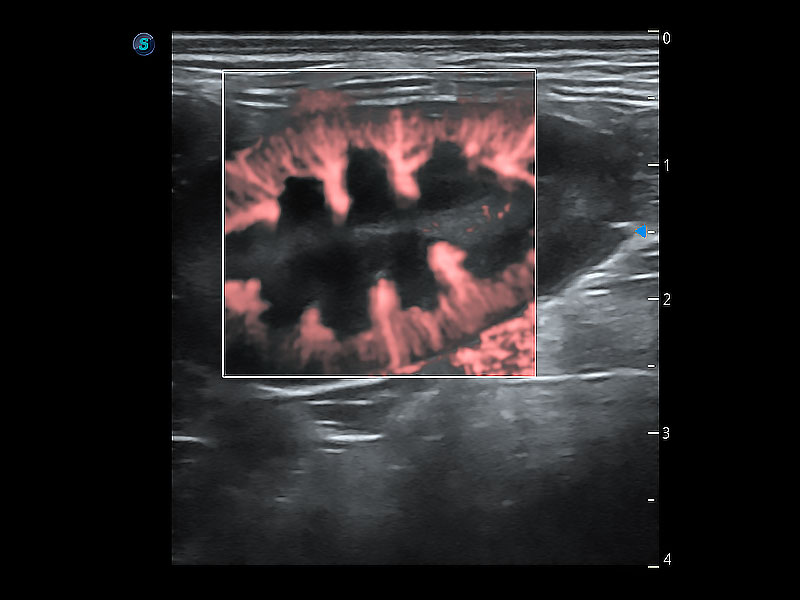

極大提升超低速微細(xì)血流的檢出能力,同時(shí)更精準(zhǔn)地濾除軟組織和超聲信號(hào),為獸用醫(yī)生提供以往無法通過常規(guī)血流獲得的疾病診斷信息。

在傳統(tǒng)二維血流成像的基礎(chǔ)上,呈現(xiàn)血流的立體感,具有動(dòng)感的生命力之美。即便是微小的血管也能輕松應(yīng)對(duì),提高了血流的視覺敏感性。